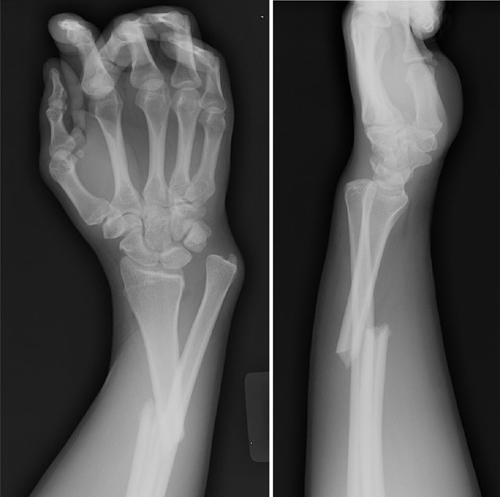

COLLES

- Dinner fork deformity

- Fracture of the distal radius with dorsal displacement and volar angulation, with or without an ulnar styloid fracture

- median nerve injury common

- usually a FOOSH